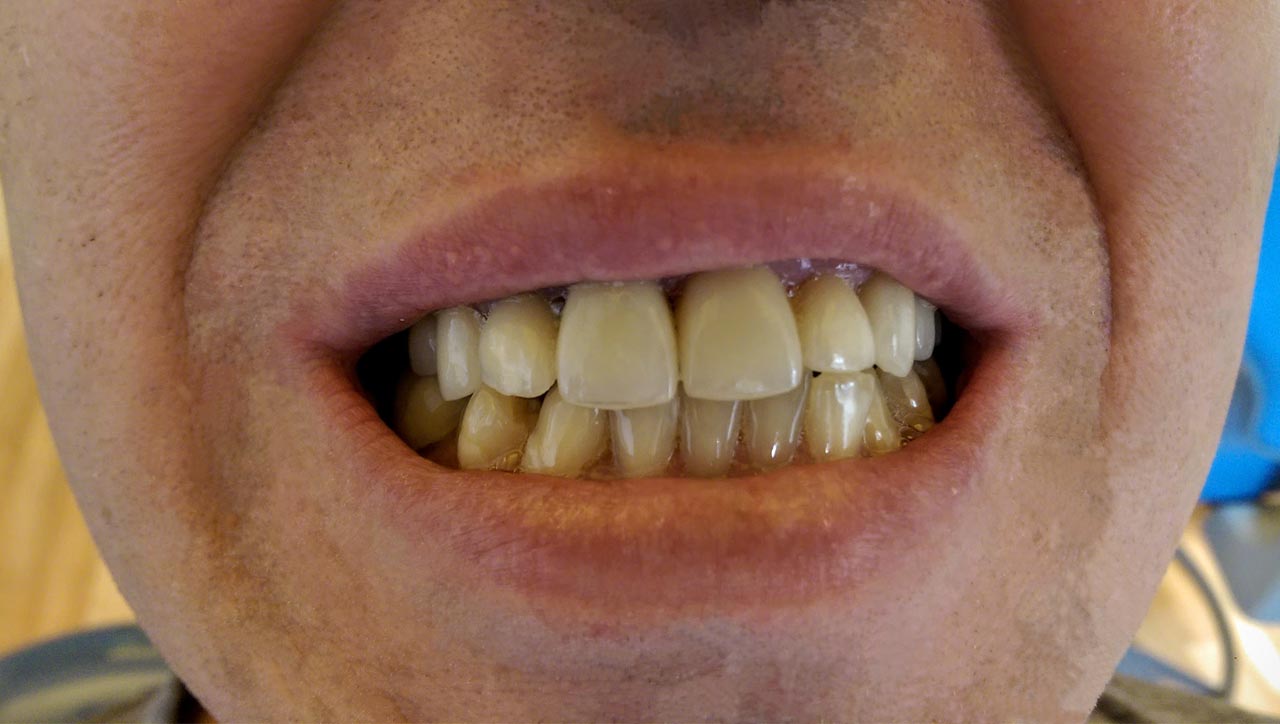

Alsó állcsont teljes rehabilitációja 72 óra alatt, azonnal terhelhető implantátumokkal súlyos paradontitisben szenvedő dohányzó páciens esetében. Az alsó állcsont fogai mind mozogtak az előrehaladott fogágypusztulás miatt.

A fogakat eltávolítottuk, a gyulladt, fertőzött csontot kitakarítottuk, kifertőtlenítettük, majd azonnal implantáltunk.

Svájci, IHDE márkájú, azonnal terhelhető implantátumokat helyzetünk be, és ezekre harmadnapra rögzített, hosszútávú, fémvázas, esztétikus műanyaggal leplezett hidat ragasztottunk be.

Ezt az ideiglenes hidat a sebek gyógyulása miatt használjuk, de tartóssága miatt véglegesként is használható. A legtöbb esetben, ahogy itt is, 6 hónap múlva porcelán hídra cseréljük, a teljes gyógyulás után.